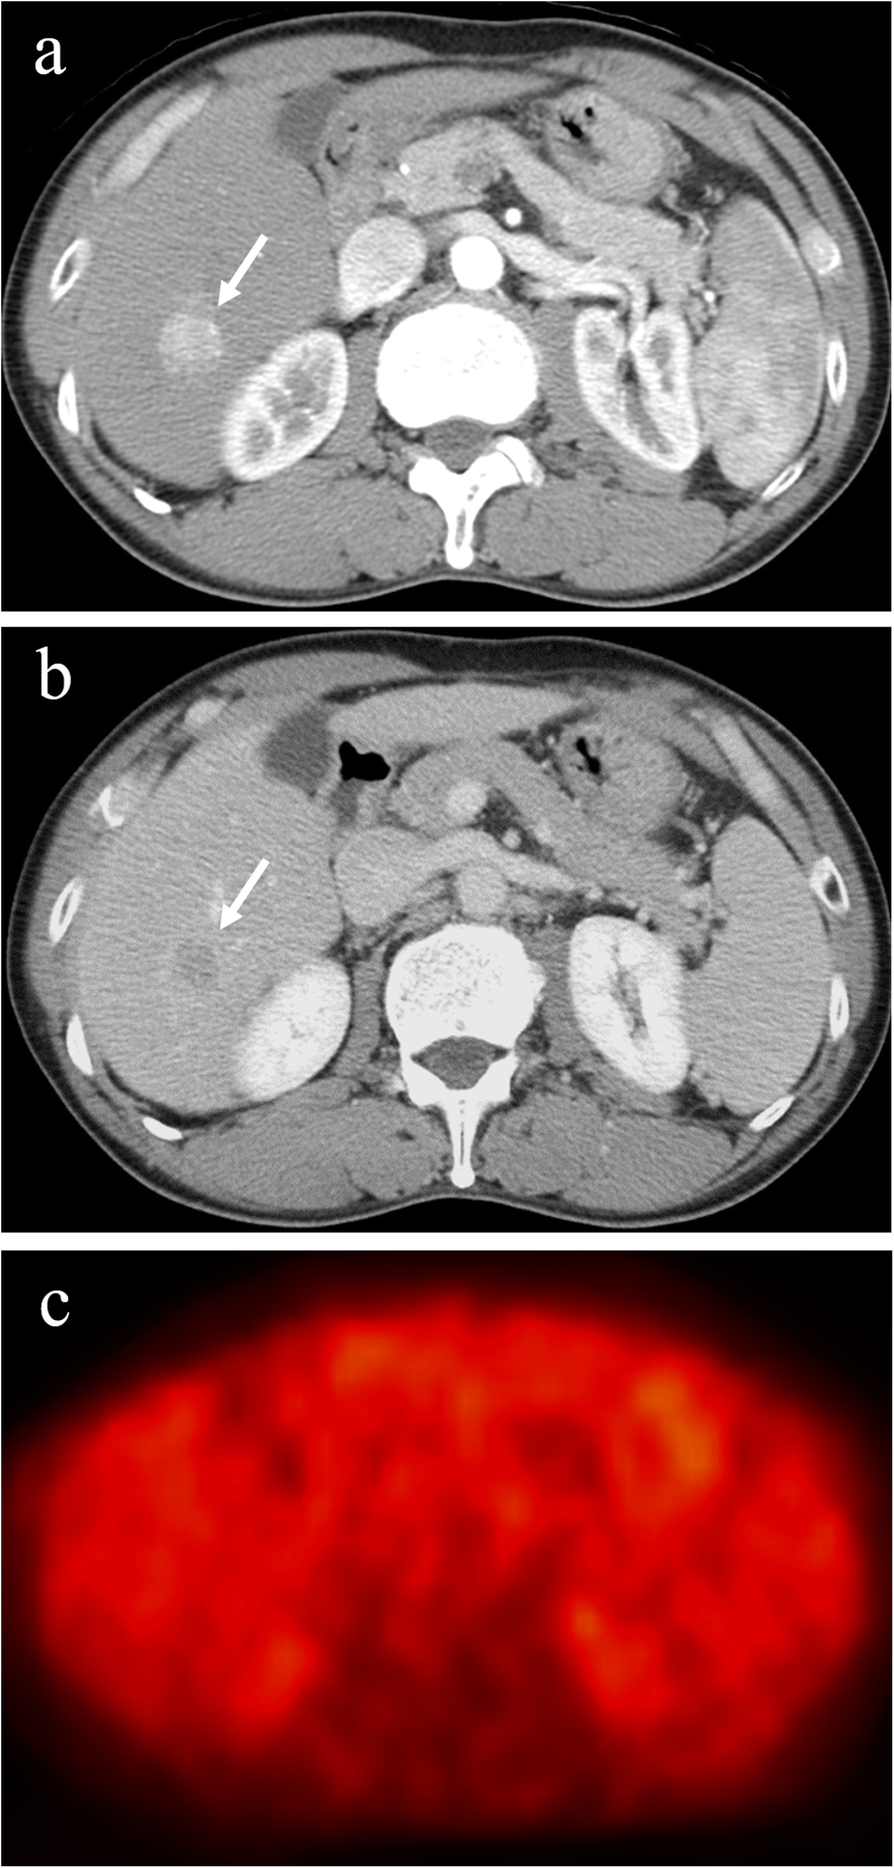

Fig. 2

Hepatocellular carcinoma with negative 18F-fluorodeoxyglucose uptake on positron emission tomography. The hepatocellular carcinoma (diameter, 2.0 cm) in segment 6 exhibits staining during the arterial phase of contrast computed tomography (a) and washout during the equilibrium phase (b). The tumor has equal 18F-fluorodeoxyglucose uptake to that of surrounding liver on positron emission tomography (c). Arrows indicate the tumor